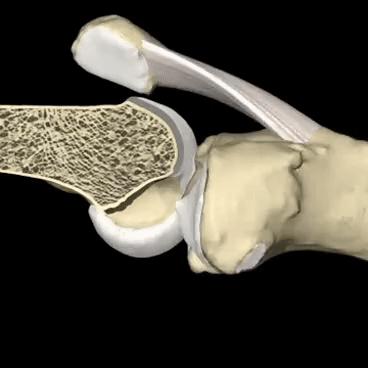

另外髌骨软骨软化比较经典的症状就是打软腿了。在走路的时候并没有什么特殊的诱因,膝盖会突然软一下,仿佛失去了对膝盖的控制一样。这个时候往往并不伴有疼痛,所以也很少有人在意,但是当症状越来越重,出现疼痛的时候再进行治疗可能就错过了治疗的最佳时机了!下图就是髌骨软骨不同程度软化的关节镜下影像学资料,看完之后,大家可能会对这个问题有一个更深的了解吧。

明确关节腔是否有软骨软化,主要靠医生的查体、患者的症状,另外需要进行膝关节核磁检查,因为软骨在x线下是不显影的,只有核磁才能看到关节腔内软骨的具体情况。